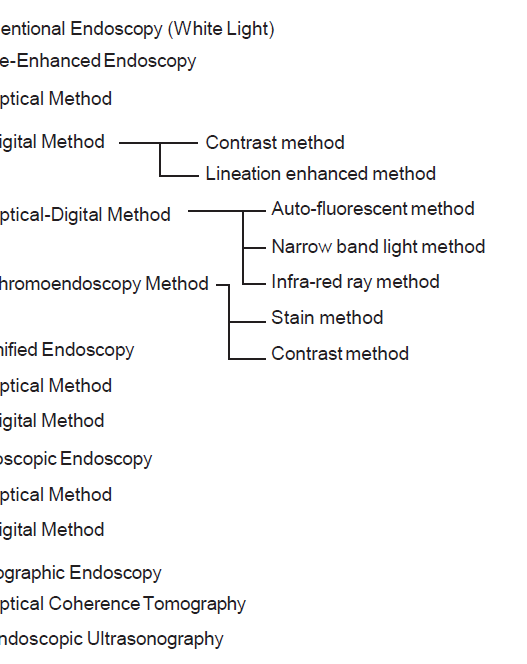

According to the morphology of the anatomical components, the MV and MS patterns were classified as regular, irregular, or absent (. Fig. 2). In principle, the MV and MS patterns must be determined separately.

DL is defined as the border between the lesion and non-lesion areas, discernible through an abrupt change in MV and/or MS patterns (. Fig. 2).

The working group members carried out a systematic review of the English literature to determine widely accepted diagnostic systems. Consequently, the best-accepted diagnostic system was proven to be the VS classification system. Based on this system, MESDA-G was constructed using an evidence-based approach (. Figs. 3, 4, 5, and 6) [2]. First, lesions suspicious for EGC should be detected by careful inspection using conventional white-light endoscopy. Subsequently, magnified observations should be performed. Owing to the high sensitivity of the demarcation line [8], if it is absent, the suspicious lesion is diagnosed as noncancerous (. Fig. 4a, b). However, if the demarcation line is present, further assessment is required to determine the presence of an irregular MV or MS pattern. If an irregular MV and/or MS pattern is detected, the suspicious lesion is diagnosed as cancerous (. Fig. 6a, b) [1, 5, 6, 8]. If both the irregular MV and MS patterns are absent, the tumor is diagnosed as noncancerous (. Fig. 5a, b) [1, 5, 6, 8].